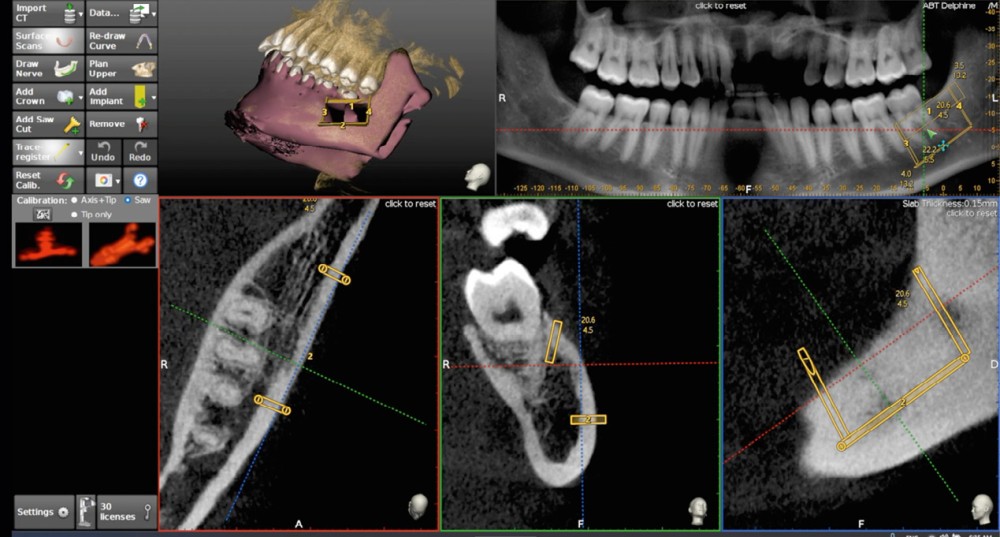

L’avènement des technologies numériques a permis d’améliorer la précision de ces procédures. La planification implantaire 3D, associée à la conception et fabrication assistée par ordinateur (CAD/CAM), permet aujourd’hui de concevoir des guides chirurgicaux spécifiques optimisant et sécurisant le positionnement des blocs osseux. De même, la démocratisation récente des techniques de chirurgie guidée dynamiques par caméra stéréoscopique constitue un outil attractif pour les techniques de reconstruction osseuse. Ainsi, la taille du bloc à prélever sur la zone rétromolaire mandibulaire peut aussi être exactement déterminée en amont de la chirurgie (fig. 1 et 2).

La possibilité de réaliser le prélèvement osseux en bloc avec un guide statique permet d’affiner sensiblement la quantité d’os prélevée en fonction du besoin réel et diminuer la morbidité du geste. En revanche, le positionnement même du guide nécessite l’ouverture d’un lambeau de grande taille.